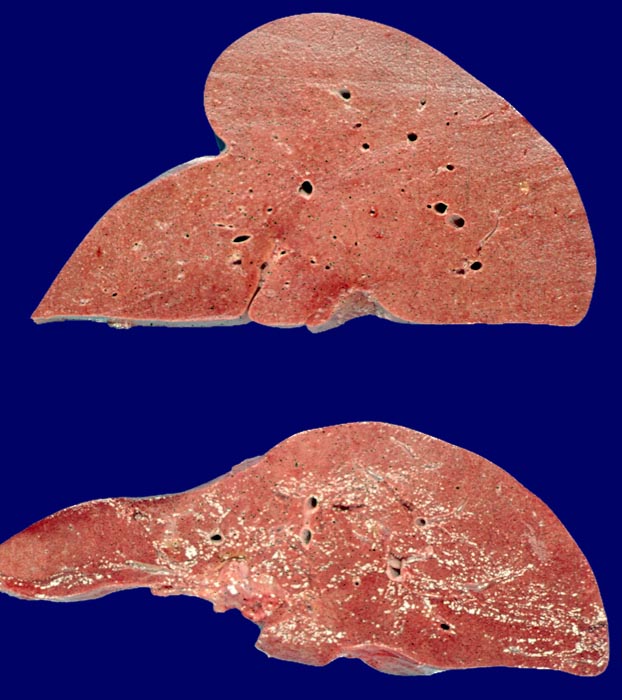

PathoPic ID 2857 - Amyloidose der Leber (oben), Normalbefund (unten)

Amyloidose der Leber (oben), Normalbefund (unten)

Die Amyloidoseleber ist vergrössert. Die Schnittfläche erscheint sehr fest, das Gewebe sehr kompakt. Unten im Bild normale Vergleichsleber.